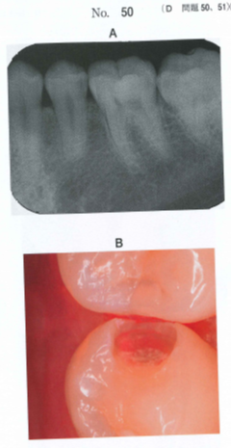

保存:109D-50,51

25歳の男性。下顎左側第二小臼歯の一過性の冷水痛を主訴として来院した。歯

髄電気診で生活反応を示した。コンポジットレジン修復を行うこととした。初診時

のエックス線写真と窩洞形成後の口腔内写真を別に示す。

50 窩洞のCファクターはどれか。1つ選べ。

a 0.2

b 0.5

c 1.0

d 2.0

e 5.0

50 写真から、左下5番の咬合面と隣接面を含むMO窩洞ということが分かります。

ということは、Cファクターは「4 / 2」で2となります。